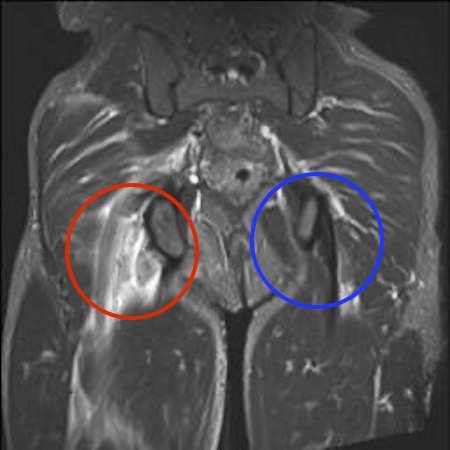

MRI

Complete / retracted tears

Proximal hamstring tear on right (red circle), normal insertion on tuberosity on left (blue circle)

Proximal hamstring avulsion on right - red circle is retracted hamstring tendon, blue circle is normal insertion on left

Proximal hamstring tear on right (red circle), normal insertion on left (blue circle)